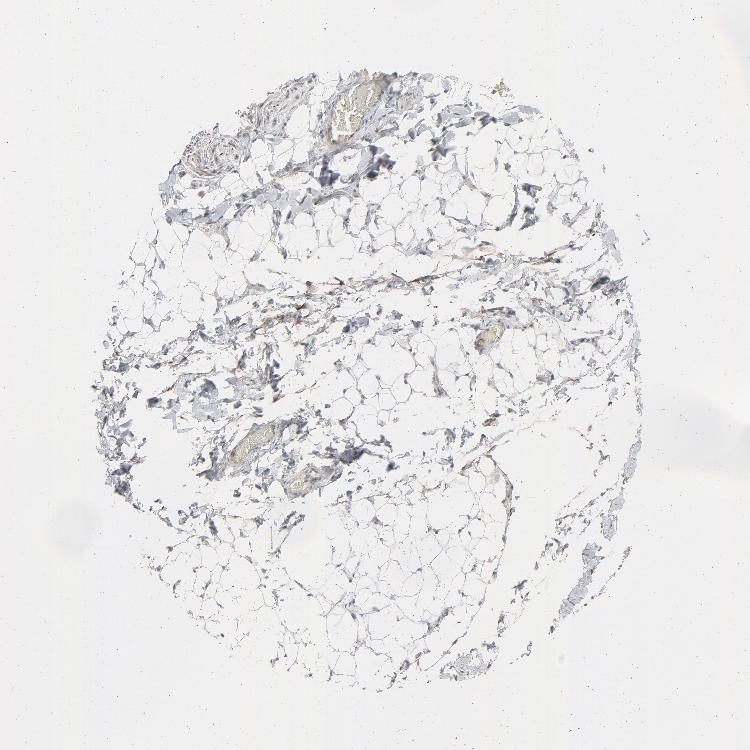

ADIPOSE TISSUE - Antibody stainingi

Antibody staining in the annotated cell types in the current human tissue is reported as not detected, low, medium, or high, based on conventional immunohistochemistry profiling in selected tissues. This score is based on the combination of the staining intensity and fraction of stained cells.

Each image is clickable and will lead to virtual microscopy that enables deeper exploration of all samples and also displays staining intensity scores, fraction scores and subcellular localization as well as patient and tissue information for each sample.

Antibody HPA003417

Adipocytes Not detected